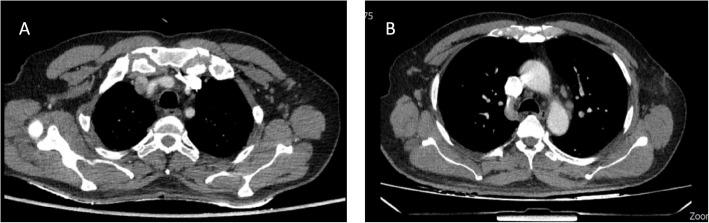

We report a 66-year-old male who developed hypereosinophilia (absolute eosinophil count: 4063 cells/µL) and lymphadenopathy two months after receiving the third dose of the BBIBP-CorV (Sinopharm) COVID-19 vaccine. Extensive investigations failed to identify an alternative cause for these findings.